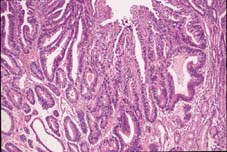

病理学的検索も、ヘマトキシリン・エオジン染色(HE染色)の形態学から広がっており、その成果を臨床の場にも取り 入れています。写真1は胃癌のHE染色、写真2は変異癌抑制遺伝子p53産物の免疫染色の陽性像ですが、癌の生物学的態度を予想する因子が一般病院の病理 検査室で染色できる時代になりました。

| 写真1 | 写真2 |